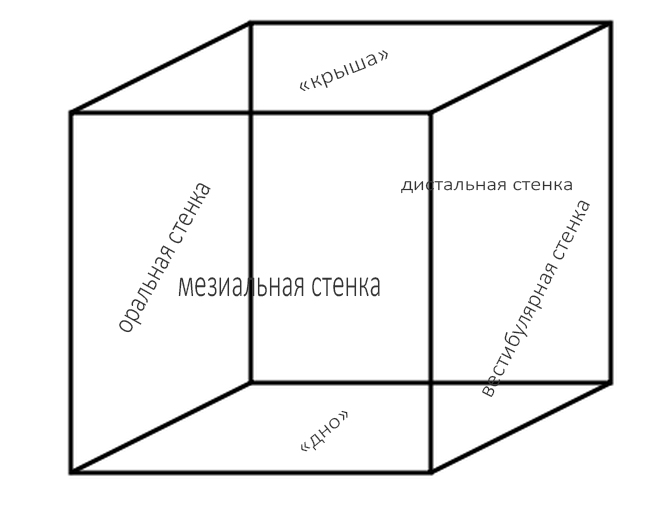

Любые костные дефекты челюстей мы можем представить в виде шестигранника (гексаэдра) или, если хотите, в виде куба:

По отсутствию одной или нескольких граней мы можем легко их классифицировать.

Например, отсутствие одной костной стенки характерно для полостей после цистэктомии:

или лунок зубов:

и т. д.